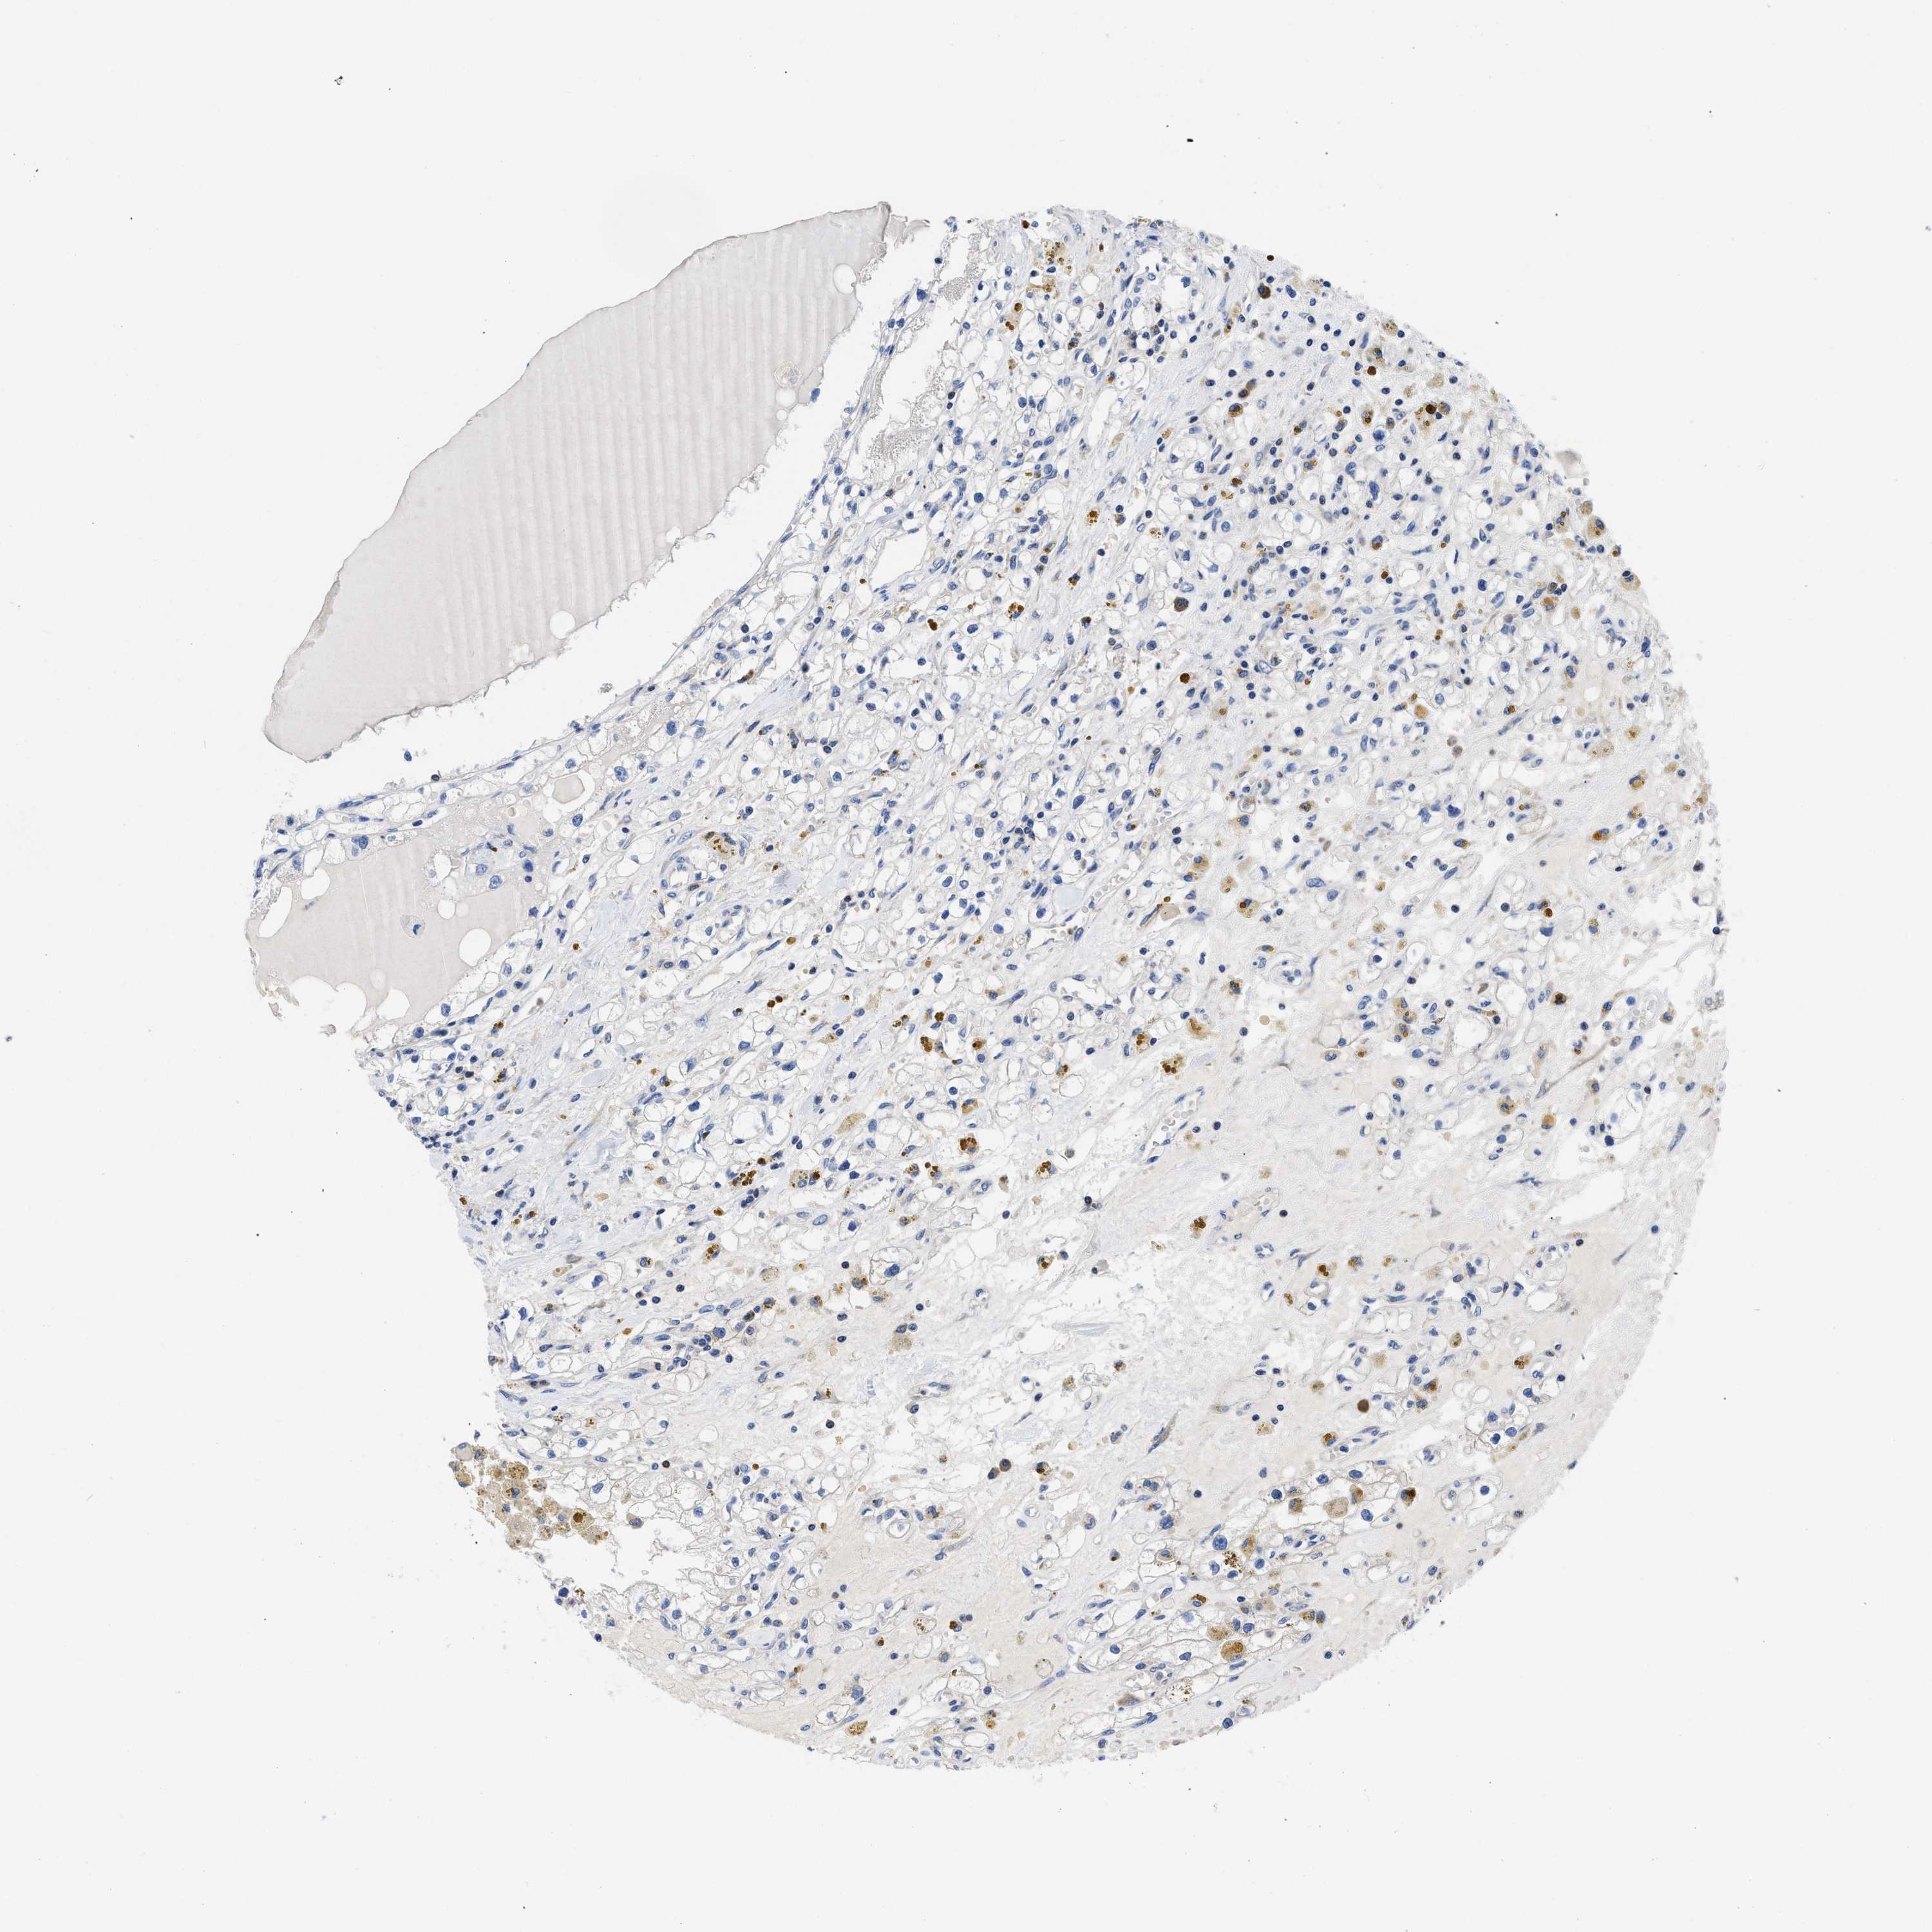

KIDNEY RENAL CLEAR CELL CARCINOMA (VALIDATION) - Interactive survival scatter ploti

The Survival Scatter plot shows the clinical status (i.e. dead or alive) for all individuals in the patient cohort, based on the same data that underlies the corresponding Kaplan-Meier plots. Patients that are alive at last time for follow-up are shown in blue and patients who have died during the study are shown in red.

The x-axis shows the expression levels (FPKM) of the investigated gene in the tumor tissue at the time of diagnosis. The y-axis shows the follow-up time after diagnosis (years). Both axes are complimented with kernel density curves demonstrating the data density over the axes. The top density plot shows the expression levels (FPKM) distribution among dead (red) and alive patients (blue). The right density plot shows the data density of the survived years of dead patients with high and low expression levels respectively, stratified using the cutoff indicated by the vertical dashed line through the Survival Scatter plot. This cutoff is automatically defined based on the FPKM cutoff that minimizes the p-score. The cutoff can be changed by dragging the vertical line or by entering a cutoff value in the square labeled "Current cut-off".

Under the Survival Scatter plot the p-score landscape (black curve; left axis) is shown together with dead median separation (red curve; right axis). Dead median separation is the difference in median mRNA expression between patients who have died with high and low expression, respectively. It is calculated as follows: median FPKM expression of dead patients with high expression - median FPKM expression of dead patients with low expression. This is intended to aid the user in visually exploring custom cutoffs and the associated p-scores and dead median separation.

Individual patient data is displayed and can be filtered by clicking on one or more of the category buttons on the top of the page. Categories describing expression level and patient information include: high, low, alive, dead, female, male and tumor stages. The scale of the x-axis can be toggled between linear and log-scale by clicking on the "x log" button. Mouse-over function shows TCGA ID, patient information and mRNA expression (FPKM) for each patient.

& Survival analysisi

Kaplan-Meier plots summarize results from analysis of correlation between mRNA expression level and patient survival. Patients were divided based on level of expression into one of the two groups "low" (under cut off) or "high" (over cut off). X-axis shows time for survival (years) and y-axis shows the probability of survival, where 1.0 corresponds to 100 percent.

YARS1 is not prognostic in Kidney Renal Clear Cell Carcinoma (validation)

Best expression cut offi

Based on the FPKM value of each gene, patients were classified into two groups and association between prognosis (survival) and gene expression (FPKM) was examined. The best expression cut-off refers the FPKM value that yields maximal difference with regard to survival between the two groups at the lowest log-rank P-value. Best expression cut-off was selected based on survival analysis .

When clicking on this number, the vertical dashed line indicating cut-off, the interactive survival plot, and the Kaplan-Meier curve will be adjusted to show results based on the best expression cut-off.

: 42.24

P scorei

Log-rank P value for Kaplan-Meier plot showing results from analysis of correlation between mRNA expression level and patient survival.

N/A

TCGA RNA samplesi

RNA-seq data is reported as average FPKM (number Fragments Per Kilobase of exon per Million reads), generated by the The Cancer Genome Atlas (TCGA) .

Normal distribution across the dataset is visualized with box plots, shown as median and 25th and 75th percentiles. Points are displayed as outliers if they are above or below 1.5 times the interquartile range. FPKM values of the individual samples are presented next to the box plot.

Average pTPM 36.0

Number of samples 100